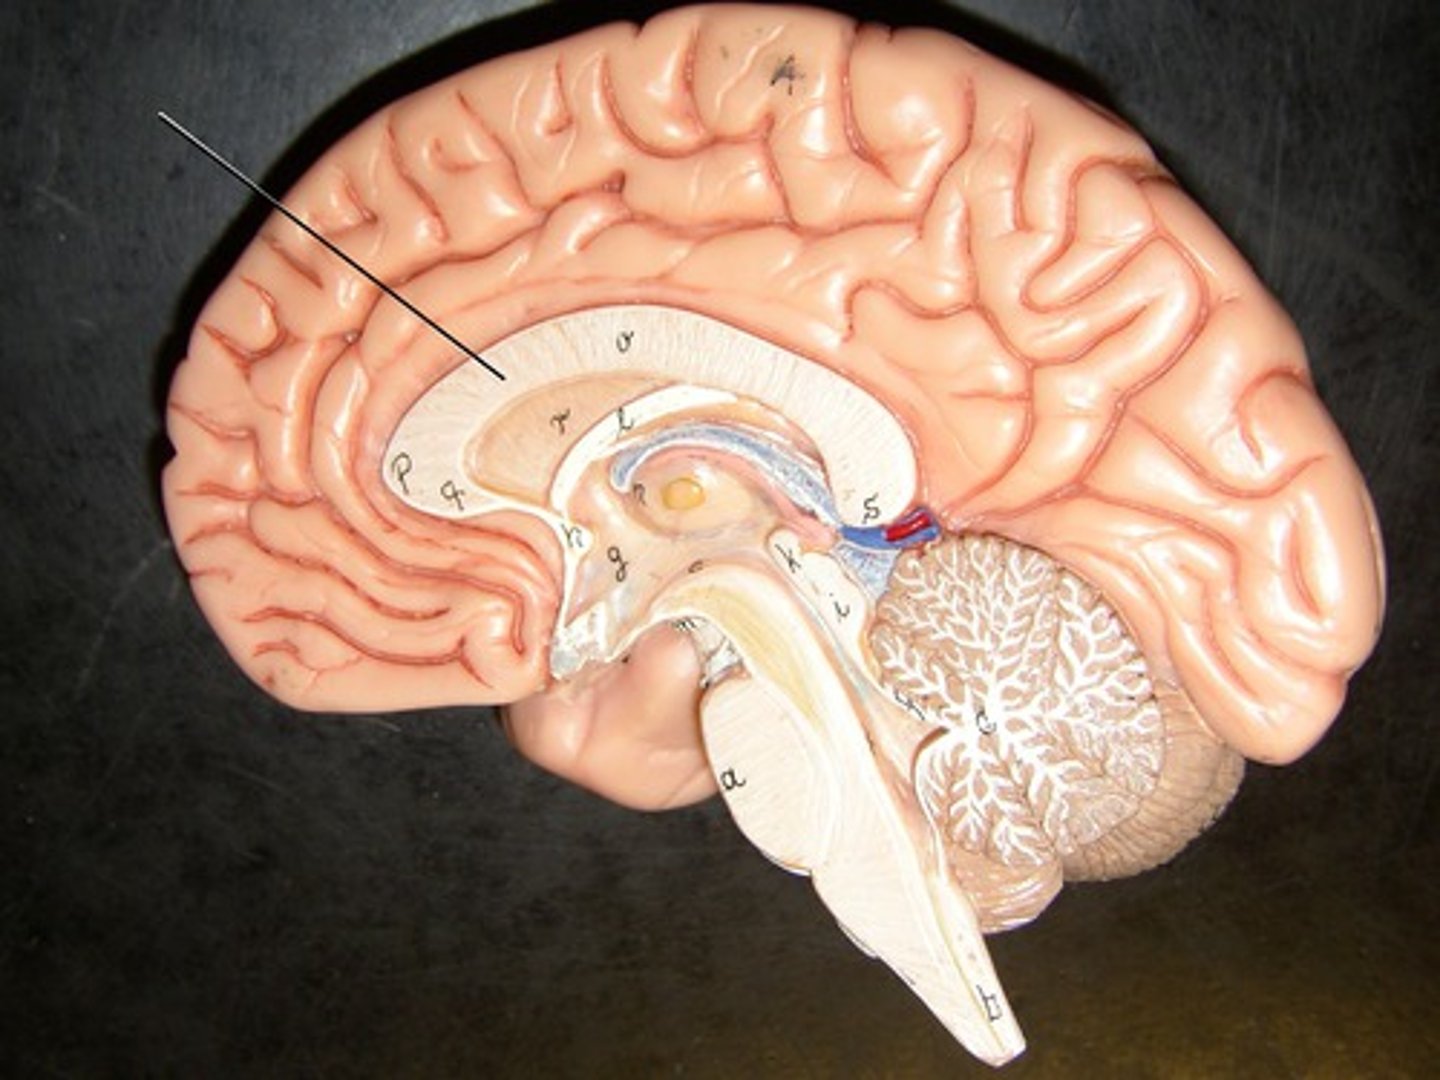

corpus collosum

part of the cerebrum. white matter. Myelinated Axons. It's job is to allow communication between the left and right hemispheres.

fornix

connects the hypothalamus and the hippocampus.

diencephalon

includes some of the area of the limbic system.

- acts as a connector in the brain.

- Connects cerebrum with the lower parts of the brain. Includes the pituitary gland, thalamus, hypothalamus, mammillary bodies, and pineal body.

pituitary gland

the thing it hangs from is the infundibulum (the stalk that it hangs from. It regulates hormones. Releases hormones that control other endocrine glands. Releases tropic hormones.

infundibulum

The stalk that the pituitary gland hangs from.

thalamus

receives and filters incoming sensory information. All the senses except for smell hit thalamus first. With generalized and specified senses.

interthalamic adhesion

in the center of the thalamus. It connects the thalamus in the right and left hemisphere of the brain.

hypothalamus

This is the big cross roads. Master control of the autonomic nervous sytem (heart rate, blood pressure, digestion, parts of urination, respiration).

- Master control of the endocrine system - secretes hormones that tell the pituitary gland what to do. Pituitary gland cannot act unless it has orders from hypothalamus.

- Makes some hormones too that it stores in pituitary gland.

- Regulation of body temperature.

- Control of emotional behavior (seat of the limbic system). Center of it.

- Helps us to integrate feelings/ have complex feelings.

- Controls food and water intake (initiates thirst mechanism) . detects blood osmolality.

- Regulation of sleep-wake (circadian rhythms).

mammillary bodies

two bumbs between pituitary gland and brain stem. Part of limbic system. Contributes to functioning of limbic system.

pineal body

considered an endocrine gland. Secretes melatonin. Plays a role in circadian rhythm - regulation of this. Sleep/wake cycles or night/day cycles. They don't know exactly how this works, but if the pineal gland does not release melatonin, you can have differences in circadian rhythm.

brain stem

Includes the mid brain, pons, and medulla oblongata.

ventricles

cavities in the brain. Includes lateral ventricles - right and left, third ventricle, fourth ventricle, cerebral aqueduct, and choroid plexus.

third ventricle

in the area where the hypothalamus is.

located beneath the arbor vitae in the cerebellum.

cerebral aqueduct

connector between third and fourth ventricle in front of colliculi.

meninges

scalp, periosteium, then, 1st meningeal layer. Includes dura mater, arachnoid mater, and pia mater.

dura mater

2 layers. Periosteal layer (outer layer) and the meningeal layer - closest to next meningeal layer. This can create the dural venous sinus. right below 1 in this picture

arachnoid mater

meningeal layer on top. 2 in this picture

pia mater

sits directly on top of brain tissue. When CSF circulates, it circulates on top of brain tissue. If you try to tear pia mater away, you'll tear brain tissue. 3 in this picture